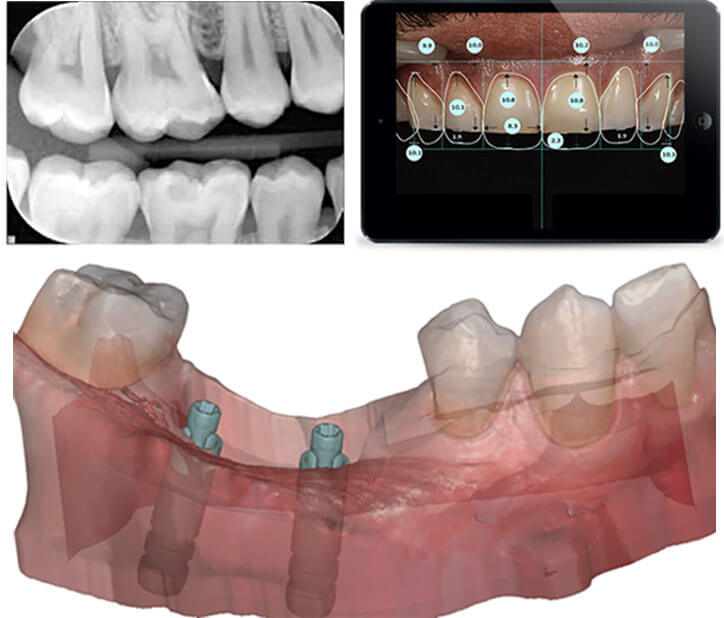

In modern day dentistry, almost every procedure can be digitized; right from caries diagnosis, to radiography, to laboratory communication, to intra- and extra-oral imaging, to smile designing, shade matching, planning implant surgeries, and even basic practice management; all can be accomplished by the various available technological advancements in dentistry.